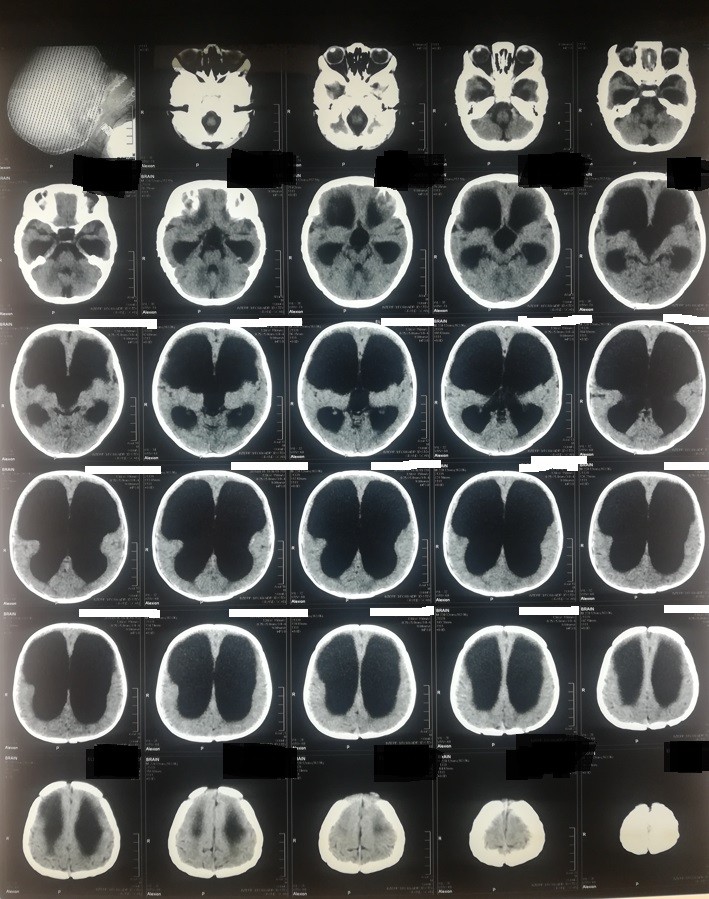

hydrocephalus in a one-year-old child and valve installation